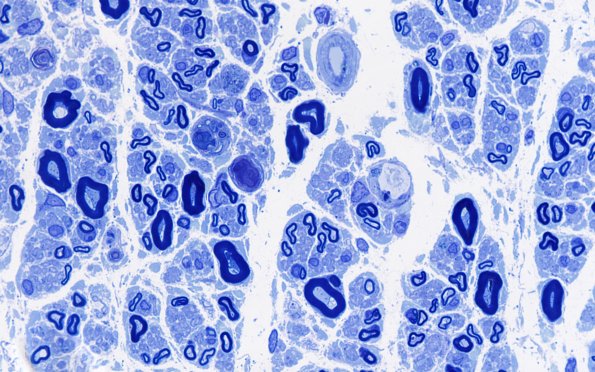

Washington University Experience | PERIPHERAL NEUROPATHY | 13 POEMS SYNDROME | 2B3 POEMS (Case 2) Plastic 100X 3

2B3,4 Degenerative changes are more consistent with axonal degeneration rather than demyelination. (Plastic sections)